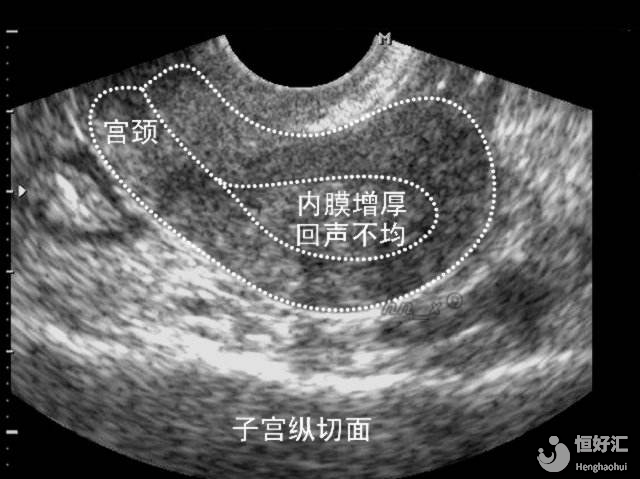

我們首先要了解一點(diǎn),子宮內(nèi)膜的厚度并未一成不變的,它會(huì)隨著月經(jīng)周期的變化而變化。在月經(jīng)期、增生期和分泌期這三個(gè)階段,都會(huì)出現(xiàn)不同的厚度變化。

子宮內(nèi)膜并不是越厚越好

子宮內(nèi)膜對(duì)試管嬰兒的妊娠成功率確實(shí)是關(guān)鍵,但并不是越厚就越好的,這個(gè)問題本身并不是絕對(duì)的。

部分研究認(rèn)為,子宮內(nèi)膜厚度越厚,那胚胎移植率就會(huì)越高;但同時(shí)也有一些研究數(shù)據(jù)表示,當(dāng)子宮內(nèi)膜厚度一旦高于14mm時(shí),胚胎移植成功率是不可觀的。